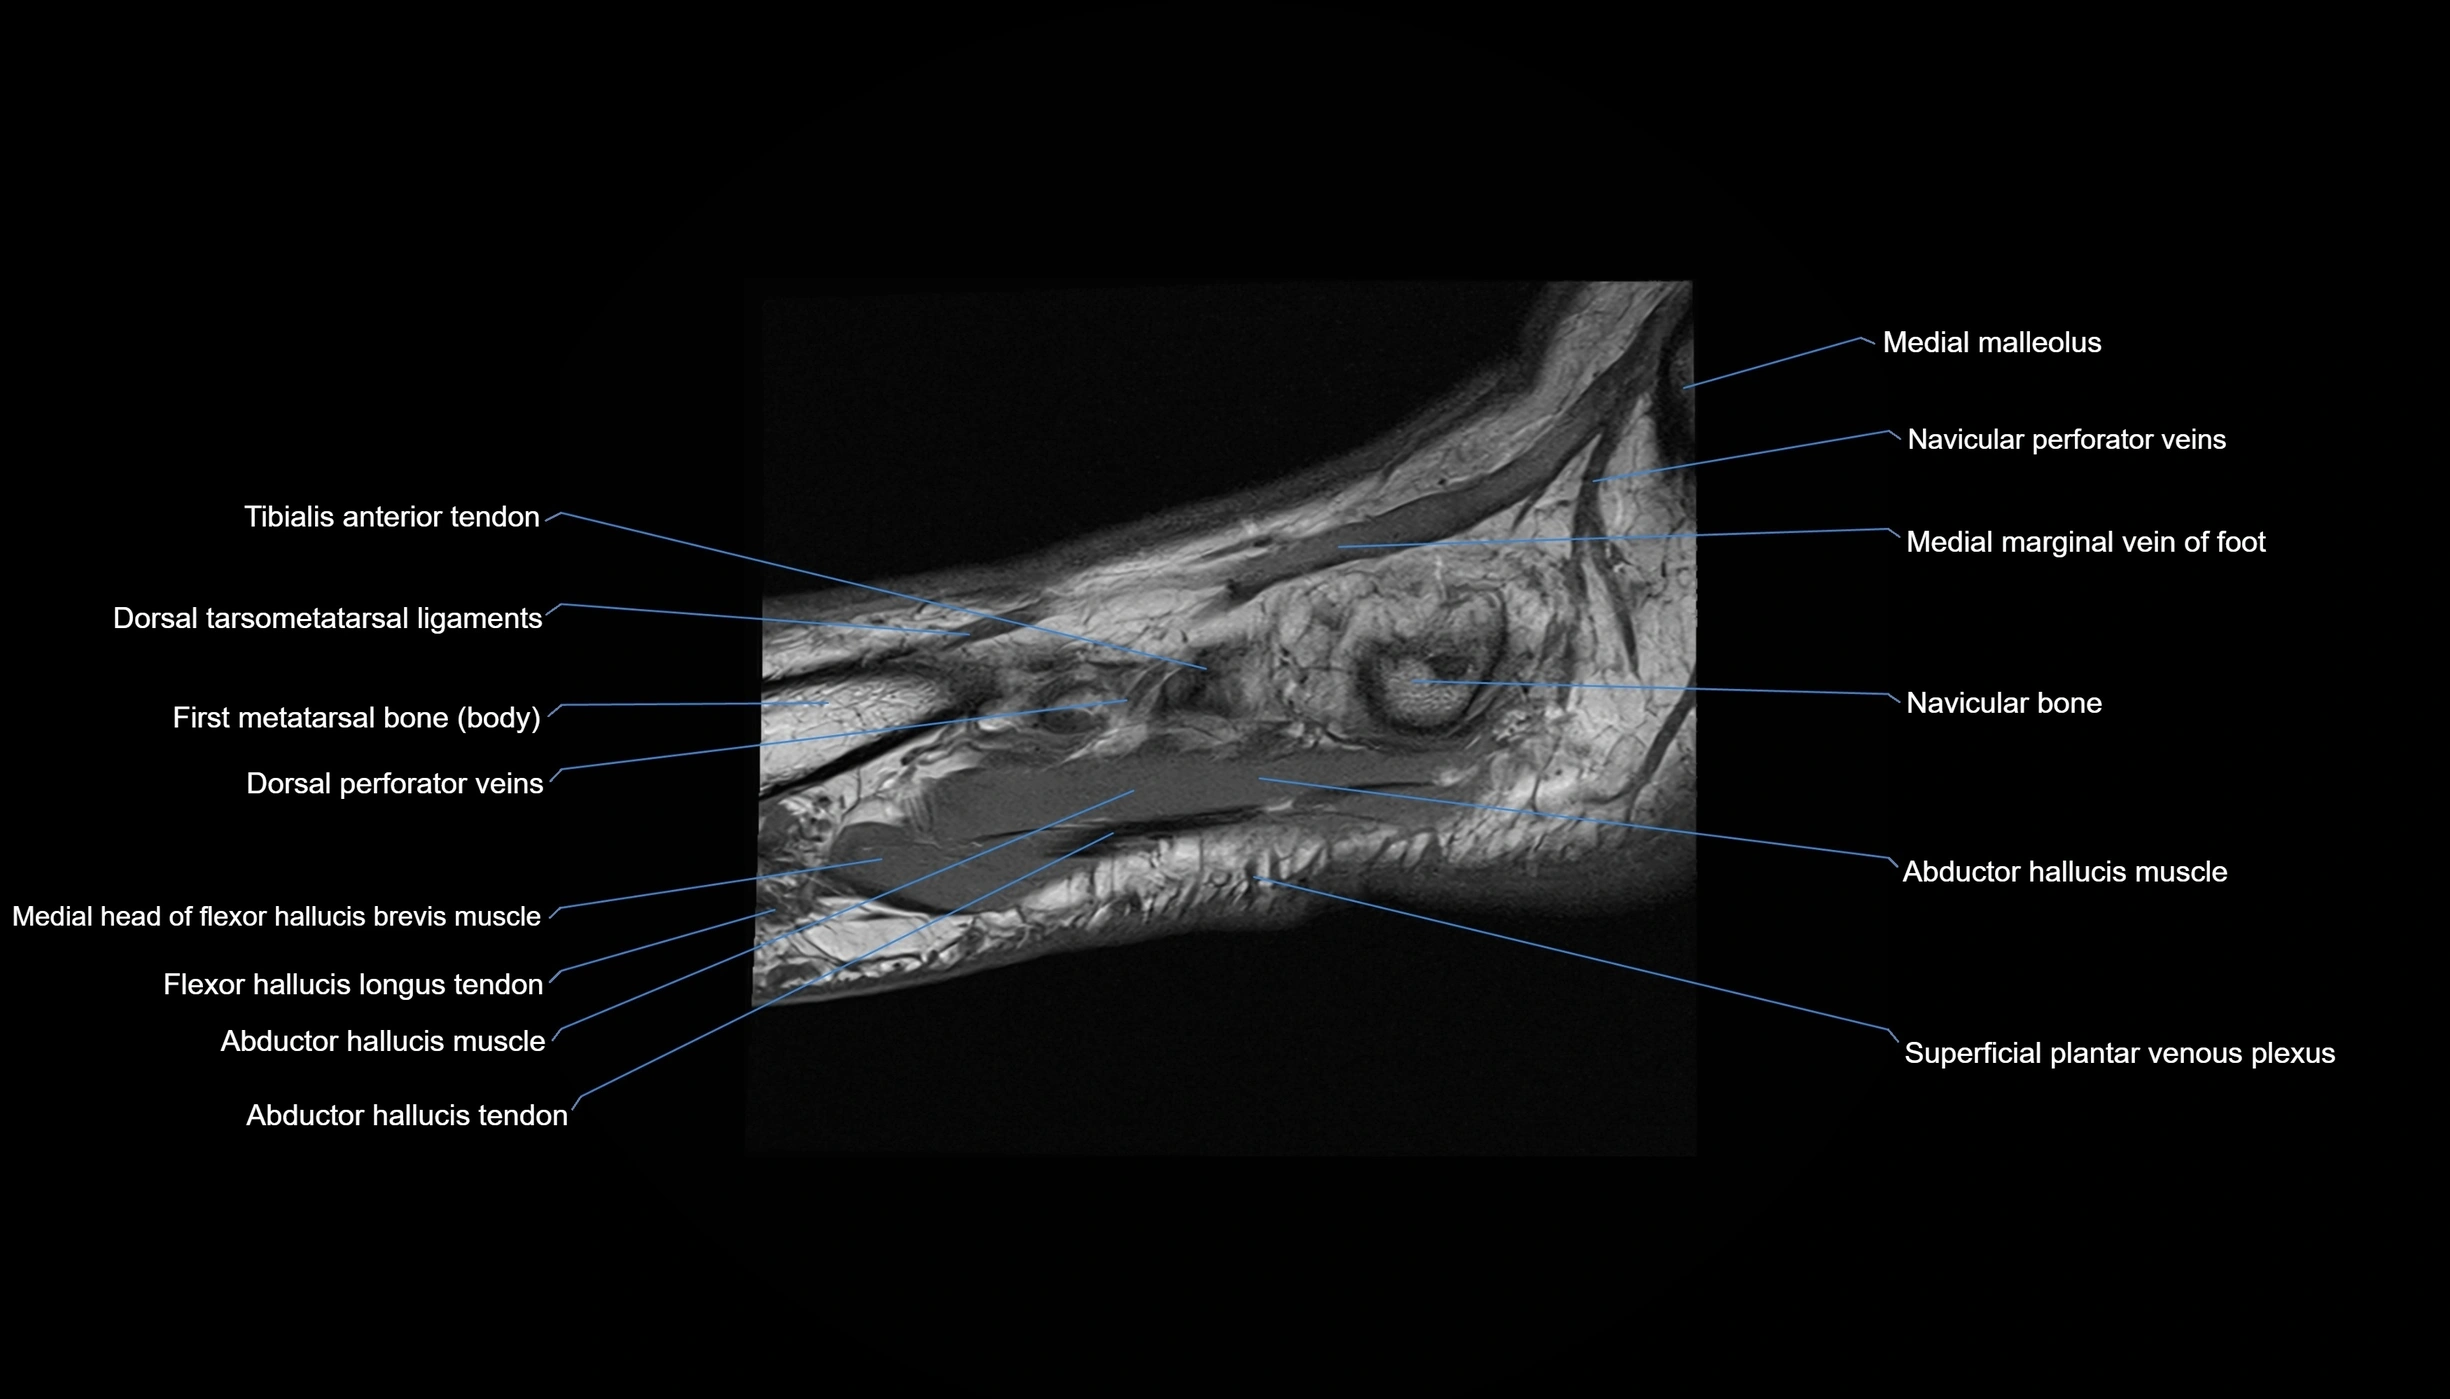

MRI image